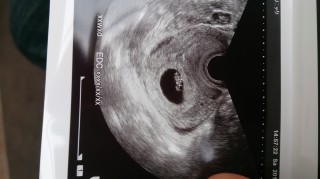

前回の診察からの2週間とても不安でした。先生に「(赤ちゃん)元気ですね」と言われ、泣きそうになりました。CRLは8.5ミリ。小さいのかな?でも前回は袋しか見えなかったのに、赤ちゃんのお弁当?も見えたし、何より心拍がチラチラしてるのが確認できて感動。次回は2週間後。今回はあまり不安ではないです。信じようー。